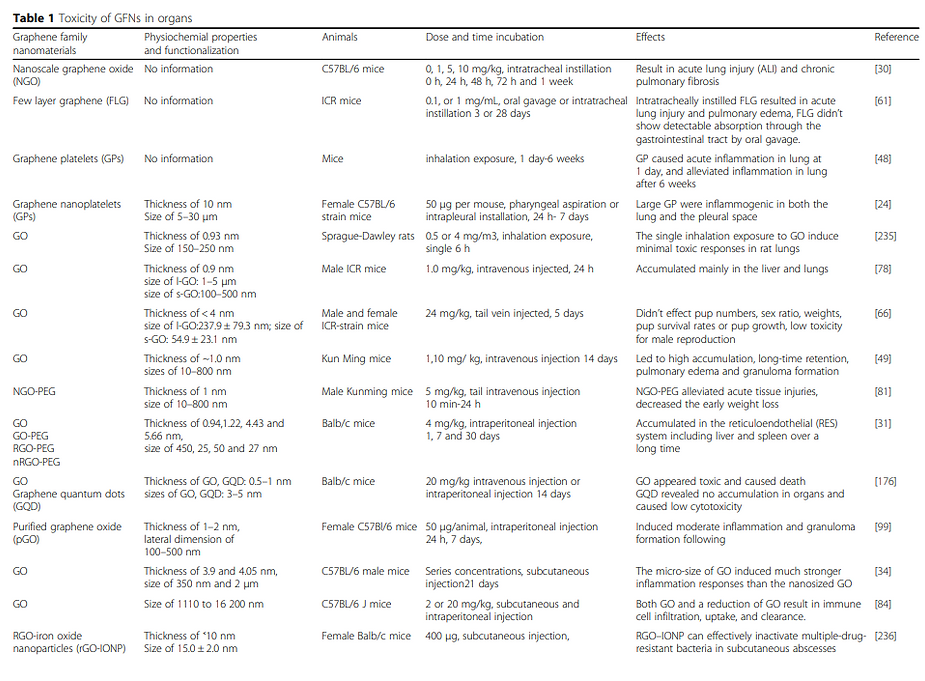

Toxicity of Graphene Family Nanomaterials

Toxicity of Graphene Family of Nanomaterials

Toxicity of Graphene Family of Nanomaterials in Cell Models

Toxicity of Graphene of Family of Nanomaterials in Cell Models

Graphene Family Nano-materials trigger local and systemic toxic effects, induce genotoxicity in vitro and in vivo, alter the gut microbiome, cause genetic mutations, and are inedible. Further toxicological and risk assessment studies are needed especially when used in food or injections of any type.

Different applications have been suggested for graphene nano-materials (GFNs) in the food and feed chain. However, it is necessary to perform a risk assessment before they become market-ready, and when consumer exposure is demonstrated. For this purpose, the European Food Safety Authority has published a guidance that has been recently updated to identify and characterize toxicological hazards related to GFNs after oral exposure. GFNs seemed to resist gastrointestinal digestion and were not able to be absorbed, distributed, and excreted, inducing toxic effects at different levels, including genotoxicity. Also, dose has an important role as it has been reported that low doses are more toxic than high doses because GFNs tend to aggregate in the digestive system, changing the internal exposure scenario. Thus, further studies including a thorough toxicological evaluation are required to protect humanity from the, as yet unknown, effects of GFNs.

Graphene, Graphene Oxide (GO), carbon nano-tubes, and the entire graphene-family nano-materials (GFN) are toxic in almost all their forms, causing mutagenesis (cancer, chromosomal alteration), cell death, apoptosis, necrosis, and the release of free radicals.

It creates immunosuppression, damage to the central nervous system, circulatory, endocrine, reproductive, and urinary systems, which can cause anaphylactic death, and multi-organ dysfunction. It increases toxicity rapidly in the lungs, creating cytokine storms leading to bilateral pneumonia, genotoxicity, and DNA damage.

Several typical mechanisms underlying Graphene Oxide nano-material’s toxicity have been revealed in numerous studies including my own, for instance, physical destruction, oxidative stress, DNA damage, inflammatory response, apoptosis, autophagy, and necrosis. In these mechanisms, toll-like receptors, transforming growth factor-beta (TGF-β) and tumor necrosis factor-alpha (TNF-α) dependent-pathways are involved in the signaling pathway network, and oxidative stress plays a crucial role in these pathways.

Many experiments have shown that Graphene Oxide nano-materials have toxic side effects in many biological applications.

According to the USA FDA, graphene, Graphene Oxide, and reduced graphene oxide elicit toxic effects both in vitro and in vivo.

Graphene-family nano-materials (GFN) are not approved by the USA FDA for human consumption.